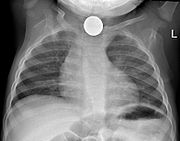

Chest X-ray showing a Canadian dollar coin in the esophagus of a young child

Prior to undertaking endoscopy, attempts should be made to locate the foreign body with x-rays or other non-invasive techniques. For radio-opaque objects, x-rays of the neck, chest and abdomen can be used to locate the foreign body and assist endoscopy. Alternative approaches, including the use of metal detectors, have also been described.

X-rays are also useful for identifying the type of foreign body ingested and complications of foreign body ingestion, including mediastinitis and perforation of the esophagus.